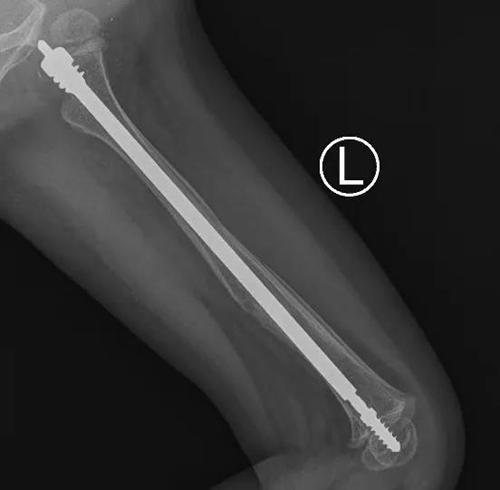

近日,青岛妇女儿童医院小儿骨科成功为一名患有“脆骨病”(又名成骨不全症)的2岁患儿进行了“左侧股骨骨折可延长髓内针内固定术”治疗,这是可延长式髓内针在省内首次应用于“脆骨症”患儿的骨折治疗。

小儿骨科团队多次讨论后,决定采用一种专门针对成骨不全的全新手术方式:儿童可延长式髓内针内固定术。这种髓内针可以应用于大腿、小腿、上臂等长骨骨折。随着孩子的生长,可延长髓内针自动滑动延长,加强了患儿骨质的强度,减少再次骨折的几率。

在完善各项检查和准备后,小儿骨科团队在麻醉科、手术室的配合下为彤彤进行了微创手术。术中,主刀医生小儿骨科主任董震将直径为3.0mm的针芯和4.8mm的可延长弹性髓内钉系统,精准的置入股骨髓腔内完成复位和固定。手术耗时仅1.5个小时,骨折部位并无手术切口,仅在远离骨折的肢体近端有个微创手术切口,术中出血仅5ml。目前彤彤恢复良好,已经康复出院。